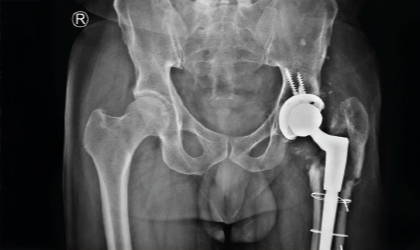

Elderly Hip Fracture Case Study

Complex Hip, Restored

This 62 year old man had a fracture dislocation of his hip following a road traffic accident.